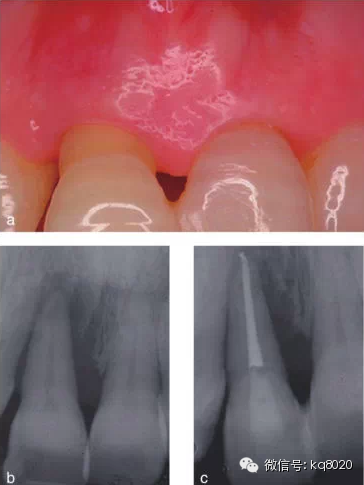

2011年,該研究團隊的隨機對照臨床試驗,選擇已經(jīng)被診斷為臨床無望、伴有牙周牙髓聯(lián)合病變、牙周附著喪失達到或超過根尖的典型病例,分別選擇采用拔牙后固定替代修復(fù)(25例)和保存再生治療(25例),進行對照,觀察遠期療效(5年);對于牙髓無活力的聯(lián)合病變患者則先行根管治療,至少觀察3個月后再行牙周手術(shù);再生治療方式包括EMD、GTR、GTR+骨粉、EMD+骨粉、EMD+GTR共5種。結(jié)果顯示,對照組和試驗組均有顯著臨床改善,牙齒功能良好,5年觀察期內(nèi)80%以上患者隨訪無不適;試驗組僅有2顆牙齒療效不佳而予以拔除,平均臨床附著增加7.7±2.8mm,X線顯示骨量增加8.5±3.1mm,PD減少8.8±3mm,均控制在4±1.7mm內(nèi),牙齒松動度均明顯減輕。

結(jié)論證實,牙周治療可改善因骨下袋缺損和重度牙周附著喪失達根尖的無望牙的預(yù)后,且這種狀況會保持穩(wěn)定5年以上(圖1、2)。